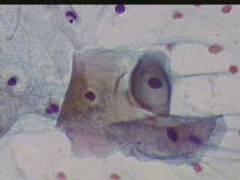

Κυτταρολογικές εικόνες προσβολής του τραχήλου της μήτρας από ιούς κονδυλωμάτων:

ασθενής 23 ετών, υποτροπές κολπίτιδος εναλλασσόμενης αιτιολογίας

Κυτταρολογικές εικόνες προσβολής του τραχήλου της μήτρας από ιούς κονδυλωμάτων: Ασθενής 23 ετών, υποτροπές κολπίτιδος εναλλασσόμενης αιτιολογίας (κολπίτις μικροβιακής αιτιολογίας, κολπίτις από Candida albicans). Τώρα: pH 5, Στο νωπό παρασκεύασμα αρραιή μικροβιακή χλωρίδα. Κολποσκοπικώς επίπεδο μωσαϊκό στο πρόσθιο χείλος. Κοιλοκυττάρωση σε επιφανειακά και διάμεσα κύτταρα. Στην μικροβιοψία τραχηλίτις, υπόνοια για HPV.